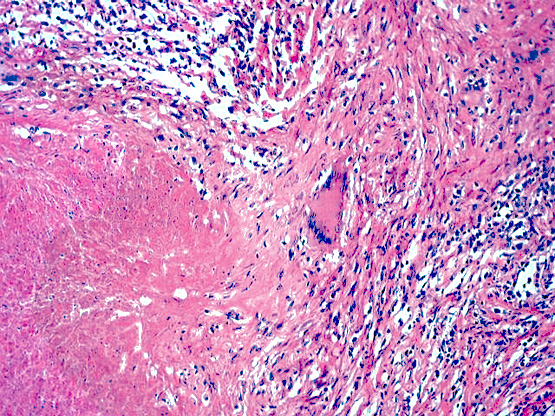

Microscopic (histologic) description

Microscopic (histologic) images

Contributed by Mark R. Wick, M.D.

Microscopic (histologic) description

- Either multiple small epithelioid granulomas or huge epithelioid granulomas with prominent Langhans giant cells and central necrosis (J Clin Pathol 1988;41:93)

Microscopic (histologic) images

Contributed by Mark R. Wick, M.D.